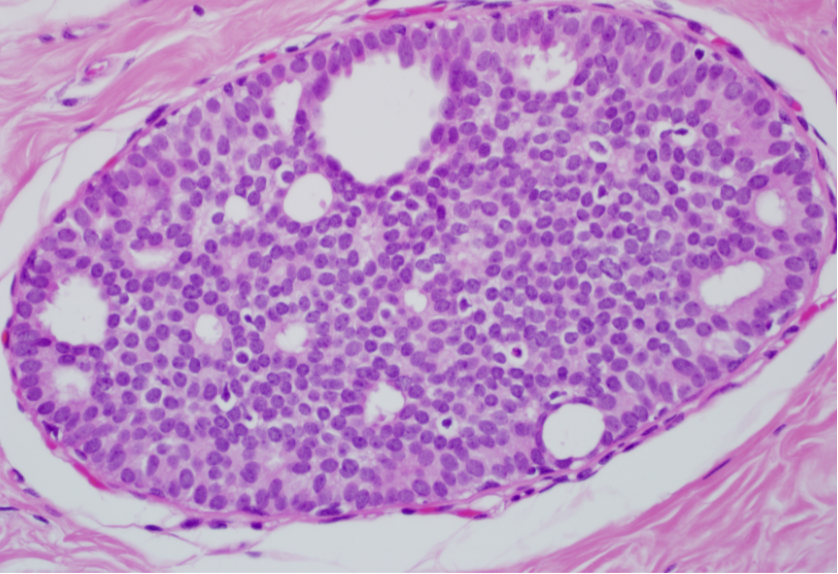

What type of pathology is indicated here?

A

Fibroadenoma

Note sharp demarcation from normal tissue, and extra glands and fibrous tissue